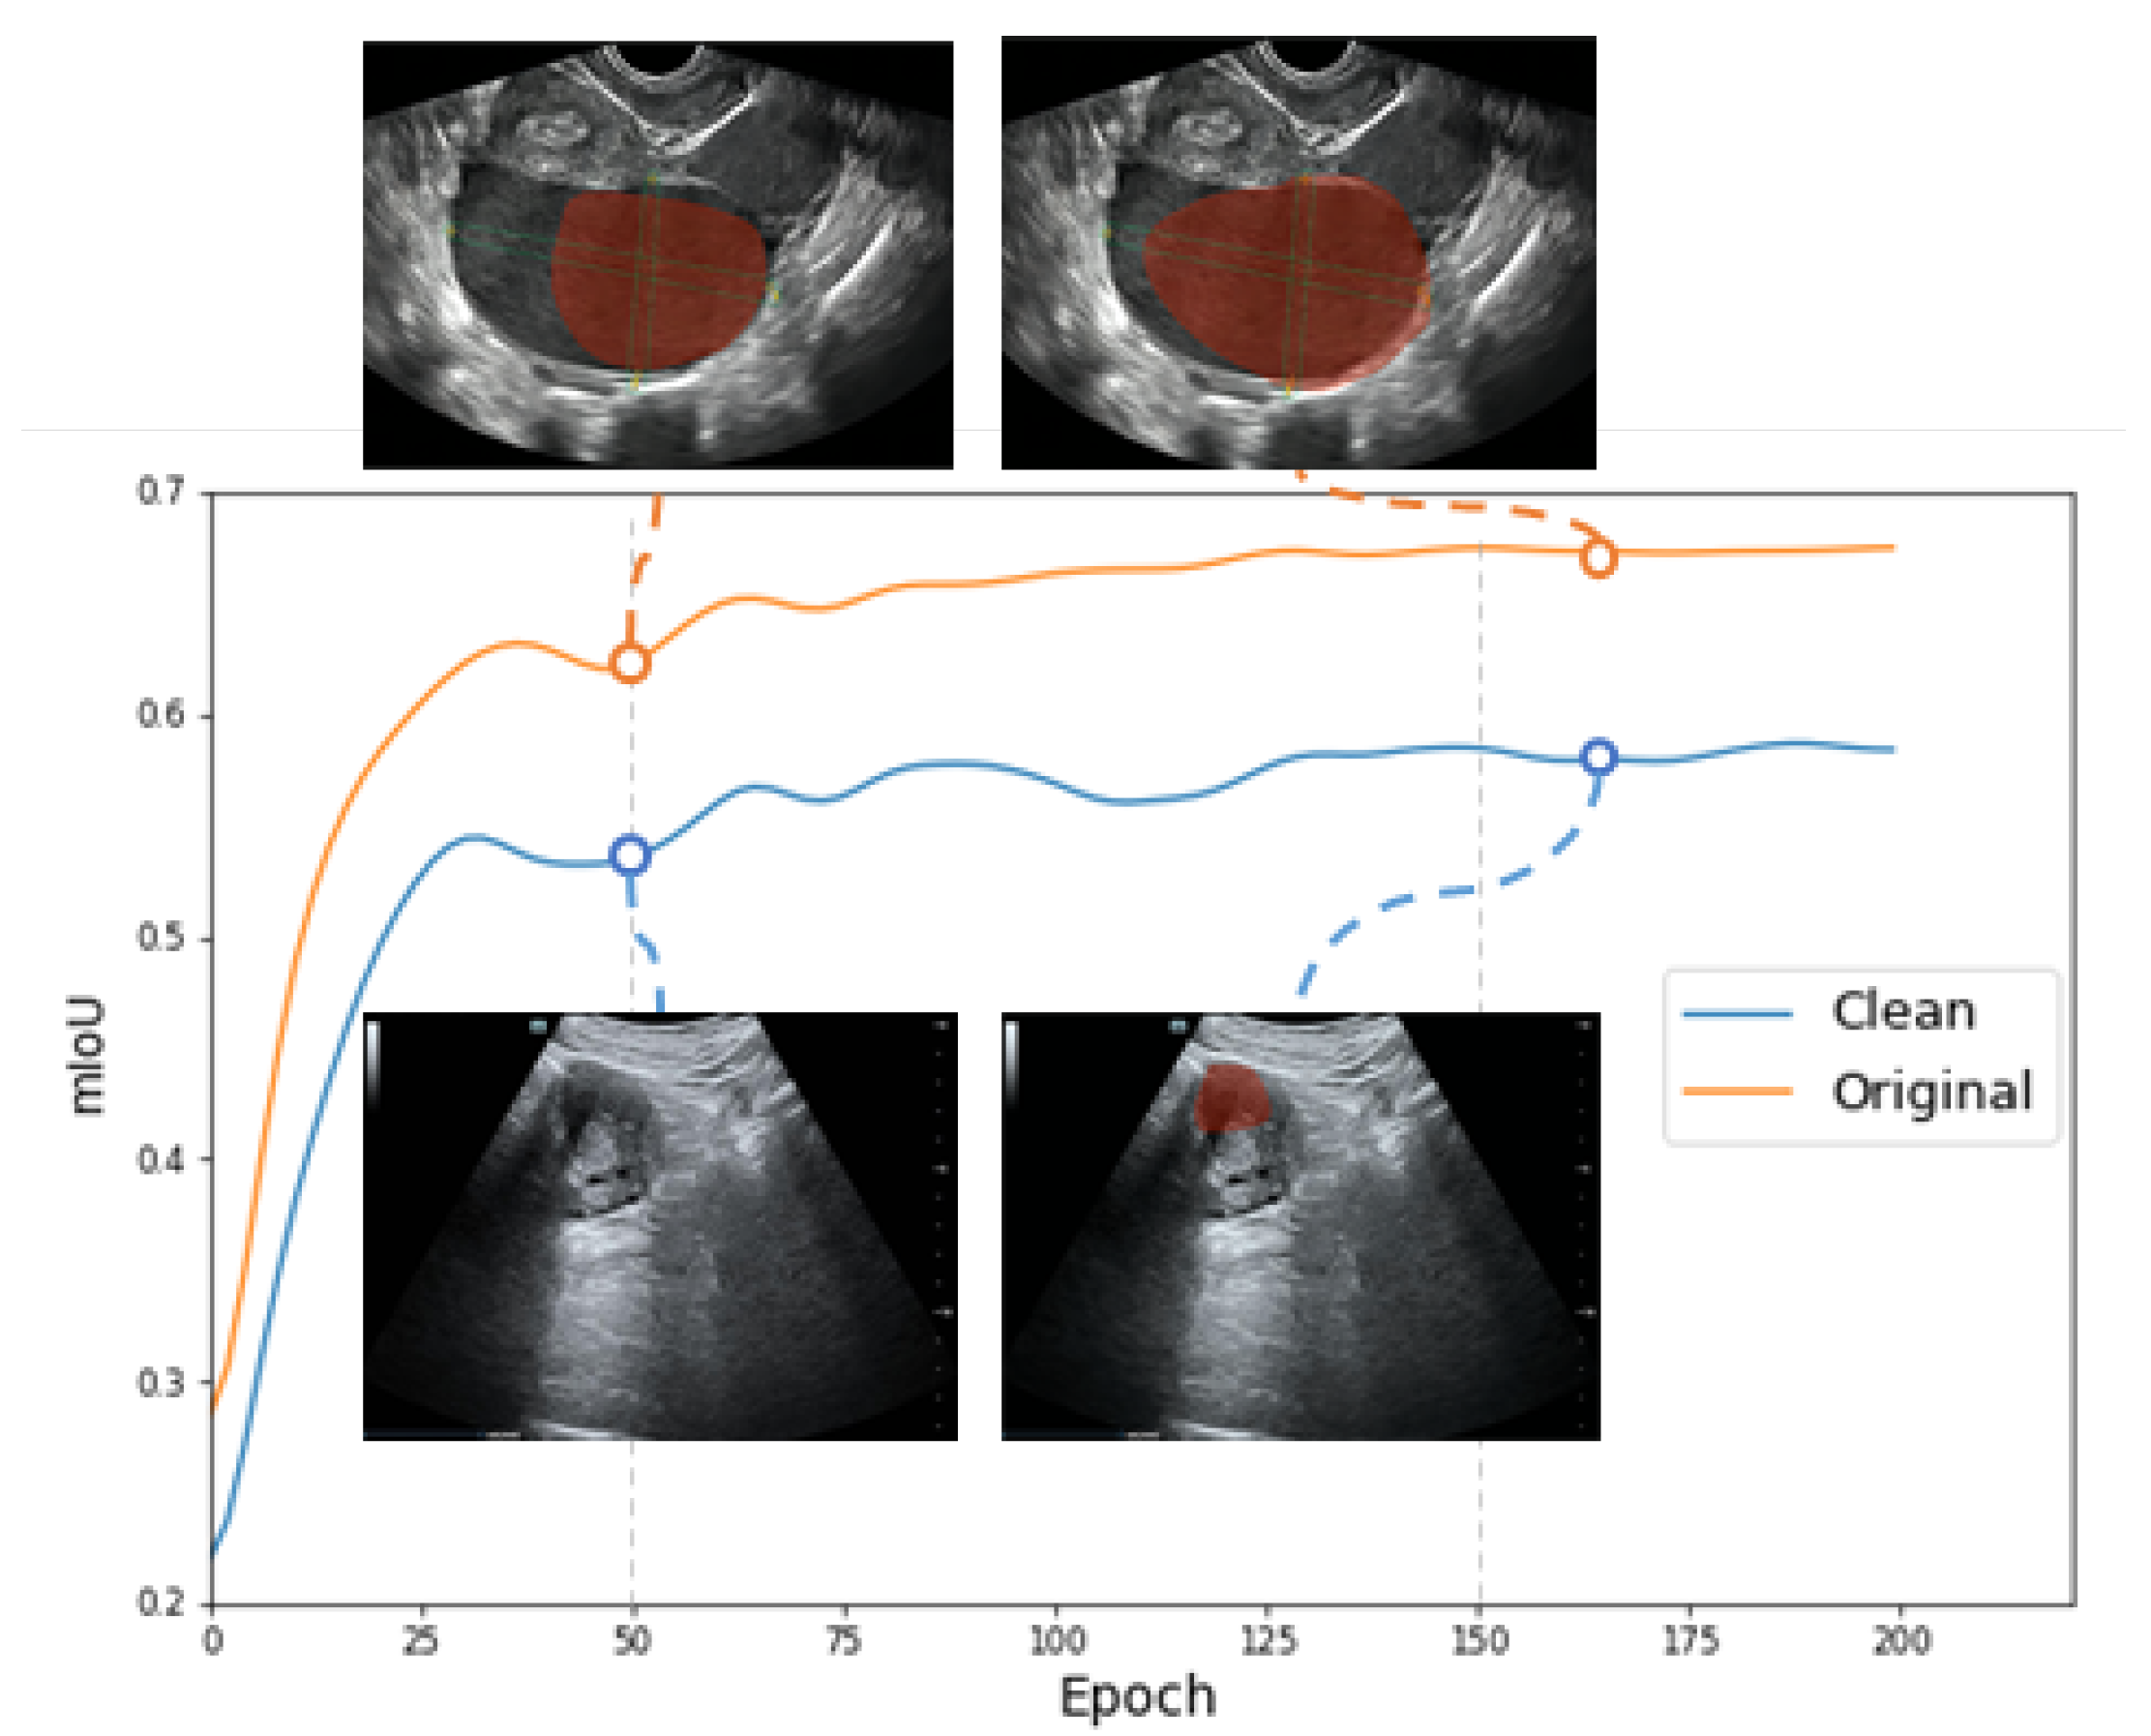

- We use the restoration images for segmentation training, which significantly enhances the accuracy of the classification and segmentation of clean images.

3.1.3. Experiments on the Lesion Segmentation